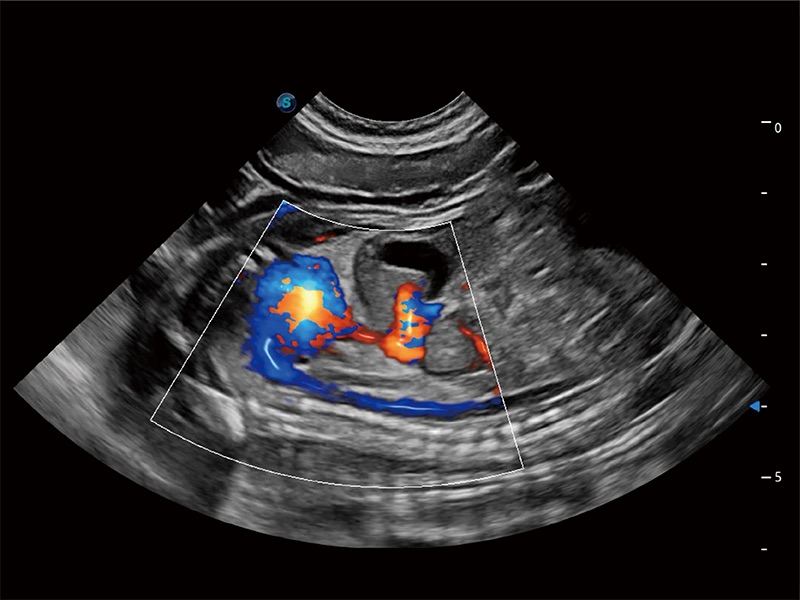

(犬)四腔心MQA

• MQA 心肌定量分析

通过心肌识别技术与二维斑点追踪技术相结合,对心脏的超声图像进行量化分析。计算心肌17个节段的应变、应变率、速度、位移等,并通过牛眼图的形式进行呈现。

优异的基础图像

ProPet 80 全新的动物超声智能软件和丰富的探头群,为动物医生提供了高清晰度和精细分辨率的图像,无论在宠物、马科、畜牧还是实验室动物等应用中都可以轻松应对,为您的日常工作带来满意的体验。